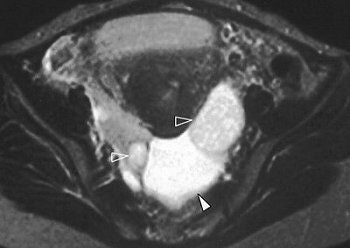

![]()  |

| Axial contrast-enhanced CT shows heterogeneous enhancement of solid components of myometrial nodules (solid arrowheads) and left adnexal peritoneal inclusion cyst (open arrowheads). |